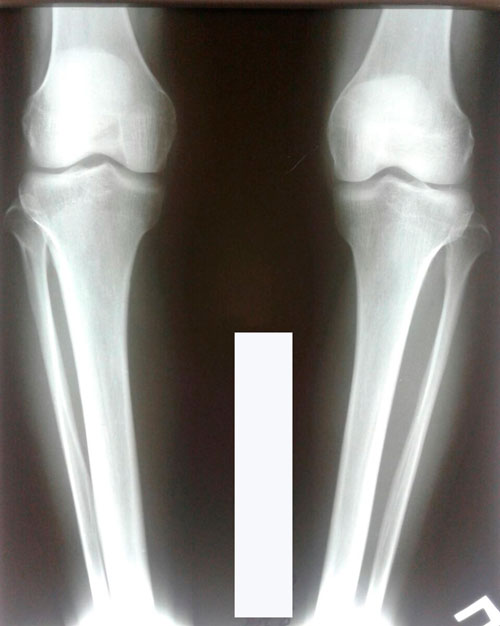

Дата операции 06.07.2017г.

Дата снятия аппаратов 05.10.2017г.

Срок лечения 90 дней.

Наталья, можете выложить сюда последний рентген? 90 дней